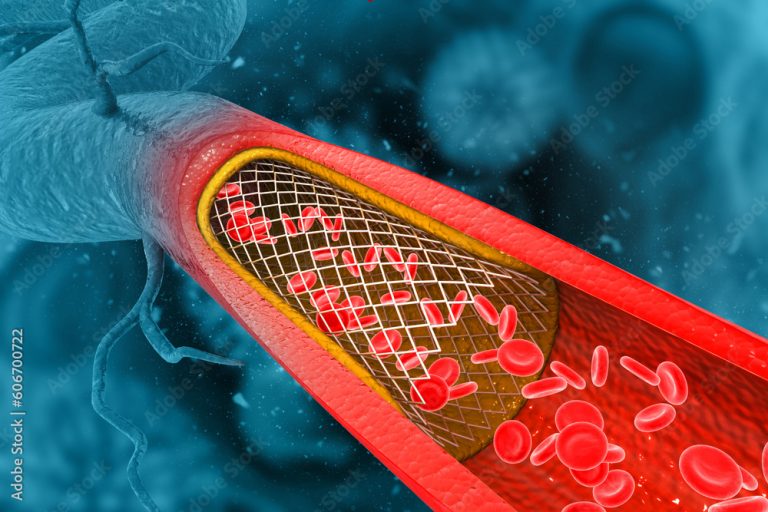

Cateterismo Cardíaco e angioplastia com Stent

O cateterismo cardíaco, também conhecido como angiografia coronária, é um procedimento médico crucial para diagnosticar e tratar doenças cardíacas. Dessa forma, desempenha um papel fundamental

CATETERISMO CARDÍACO COMO É FEITO E QUAIS RISCOS?

O cateterismo cardíaco é um exame invasivo utilizado para diagnosticar e, em alguns casos, tratar doenças cardiovasculares, como a doença arterial coronariana. Segundo as diretrizes